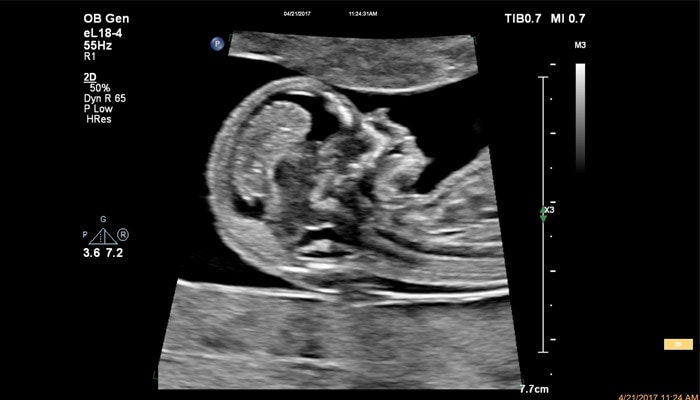

Применение eL18-4 в I триместре беременности

Детальная анатомия плода и ранняя диагностика пороков в I триместре

Линейный матричный датчик eL18-4 позволяет получить детальную информацию об анатомии плода и выявить пороки на ранней стадии развития. Сверхширокополосная PureWave матрица датчика генерирует частоты в диапазоне 2-22 МГц, что формирует одинаково высокоинформативные, четкие изображения по всей глубине сканирования до 14 см.

Высокочастотный датчик Philips eL18-4 содержит решетку из 1920 активных монокристаллических пьезоэлементов, выполненных по усовершенствованной технологии PureWave. Это обеспечивает высокодетальную 2D визуализацию, которая в совокупности с глубиной сканирования необходима для уверенной диагностики в акушерстве.

Использование линейного матричного датчика eL18-4 при осмотре беременных в I триместре, особенно на ранних сроках, позволяет ограничиться трансабдоминальным сканированием вместо трансвагинального и при этом получить максимально полную диагностическую информацию. Отсутствие полостного исследования чрезвычайно важно для соблюдения принципа ALARA – использования минимальной необходимой мощности для безопасности пациента. Благодаря применению мультичастотного датчика с диапазоном от 2 до 22 МГц через переднюю брюшную стенку хорошо определяется эмбрион длиной 3 мм, что соответствует шестой неделе беременности. В конце I триместра с eL18-4 достаточно отчётливо визуализируется четырёхкамерный срез сердца, мочевой пузырь и сосуды пуповины, которые, как правило, определяются только при трансвагинальном сканировании.

Во II триместре беременности высокая разрешающая способность eL18-4 позволяет детально изучить структуру органов и тканей и увидеть многие нюансы, которые при работе другими датчиками не обнаруживались или становились очевидны в более поздние сроки. Например, у 19-недельного плода визуализируется перегородка носа, мышцы языка, диафрагма между грудной и брюшной полостью, на 20-й неделе чётко определяются оболочки спинного мозга и уретра, а на 24-й – хорошо дифференцируются корень лёгкого, борозды и извилины мозжечка и многие другие структуры.